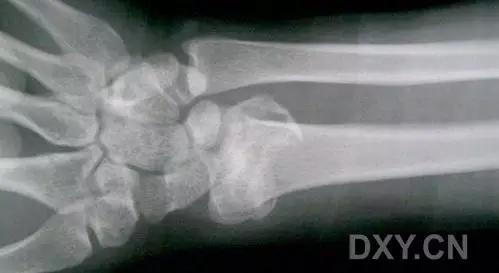

6. Bennett 骨折

第 1 掌骨基底的斜形骨折,掌骨近端形成轴向移位,掌侧边缘形成三角形的骨碎片。

(来源:Radiopaedia)